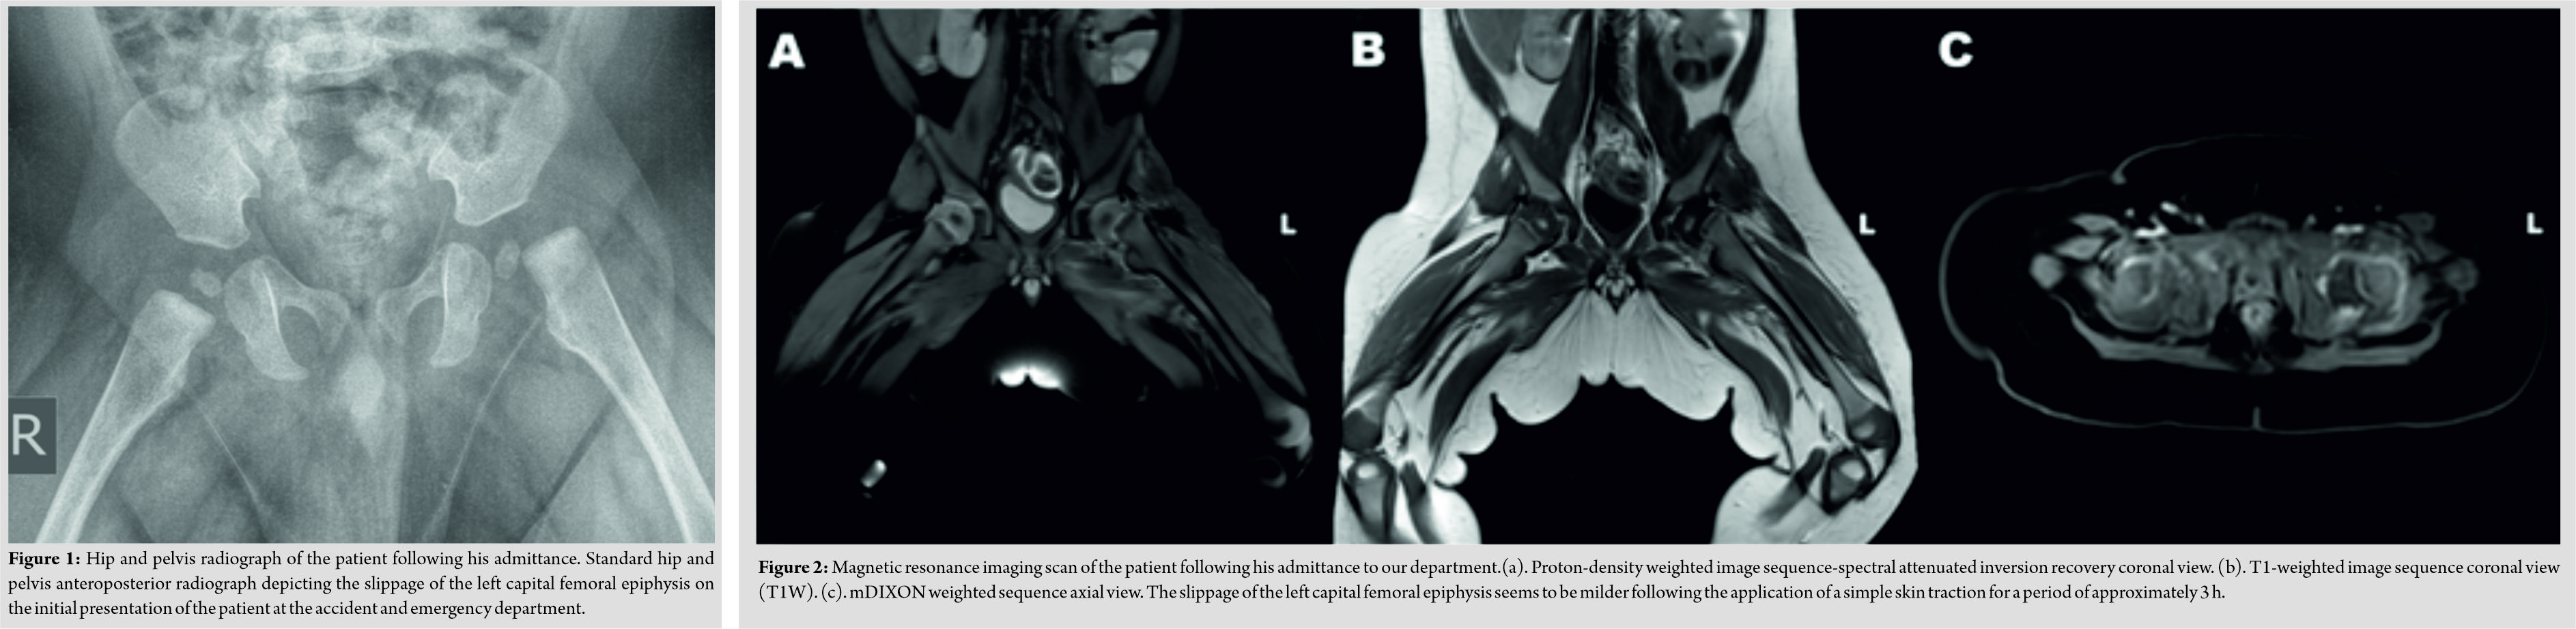

Physical examination revealed an otherwise healthy infant, with normal weight, height, and cranial perimeter for his age. The patient’s lower left limb appeared to be in pseudoparalysis;it remained in external rotation and every attempt to passively move it was painful. Routine blood test results (including inflammatory markers) were all within normal range. However, a radiograph revealed the existence of SCFE in the left hip (Fig. 1). A skin traction was put in place for analgesia and as a means to initiate– if possible– reduction of the fracture and the patient next underwent amagnetic resonance imaging (MRI)scan (Fig. 2), which confirmed the SCFE and excluded any other pathology.